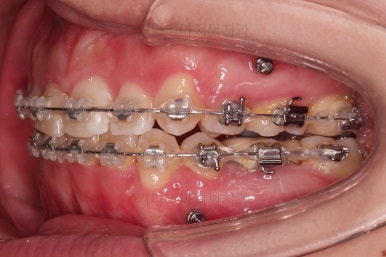

밀고 당기기를 조절하기 위해서 미니스크류도 사용합니다.

이 뽑은 공간을 자연스럽게 줄여 나갑니다.

지금부터는 입이 안들어가도록 주의하며 남은 자리를 모으고 교합을 맞춰줍니다.

오히려 이 때 부터가 훨씬 어려운 과정입니다.

미니스크류를 적절히 이용해서 어금니를 앞으로 당겨주기도 하면서 입매를 유지하며 교합을 맞춰줍니다.